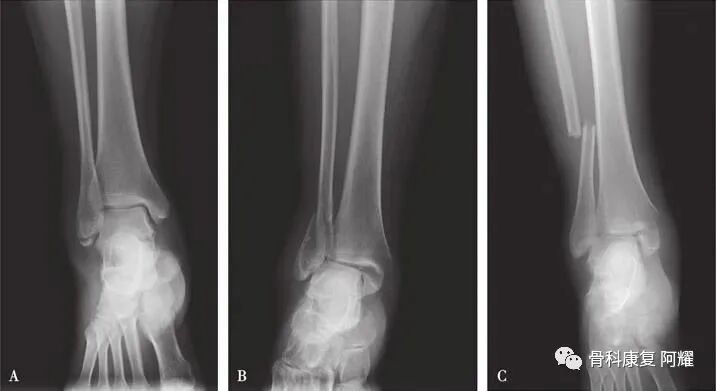

Danis-Weber分类A. A型骨折;B. B型骨折;C. C型骨折